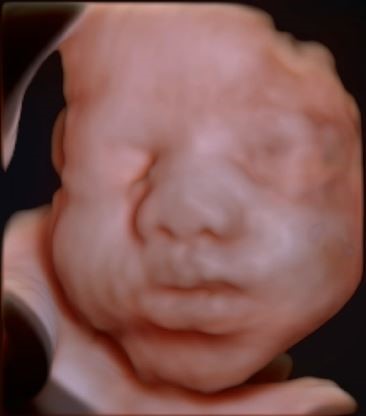

The scan is performed by the doctor in a dimly lit room to get good images of the baby. You will be asked to lie down on the couch, expose your tummy and tissue paper is tucked around your clothing to protect it from soiling due to the gel used. Ultrasound gel is put on your tummy and the doctor moves a probe over the skin. You could watch the scan on the screen in front of you. The scan does not hurt you but slight pressure needs to be applied occasionally to get a better view of the baby. You will be asked to inform the doctor if it hurts you during the scan. In advanced centers like ours, a 3D/4D probe is used to see the parts of your baby and for detailed examination.

You will be informed about the results soon after your scan along with a printed report & a few images of your baby to take home.